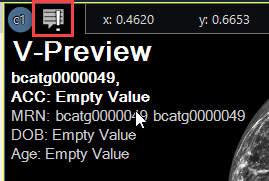

A DICOM információs panel frissült, hogy megfeleljen az Evo nézegető megjelenésének és hangulatának. A panel tartalmaz keresési funkciókat, vágólapra másolást és overlay hozzáadása opciót.